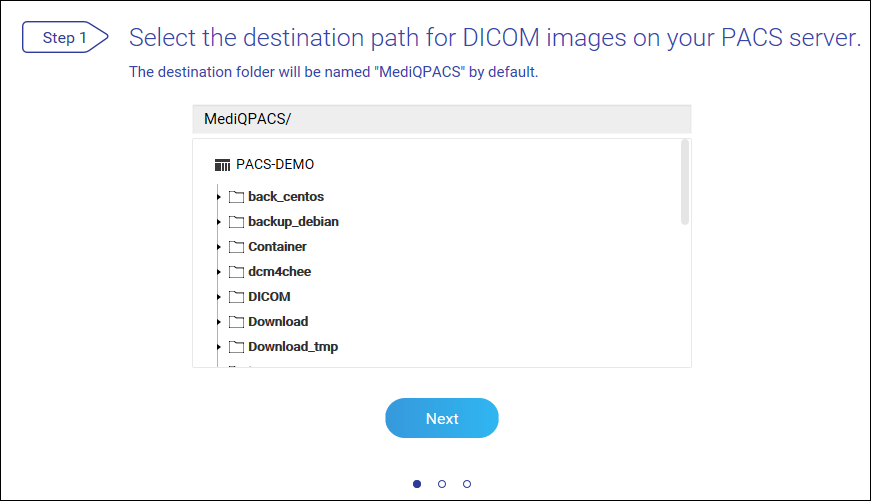

将 NAS 设置为 PACS 服务器

首次登录后,MediQPACS 管理员必须将 NAS 初始化为 PACS 服务器。